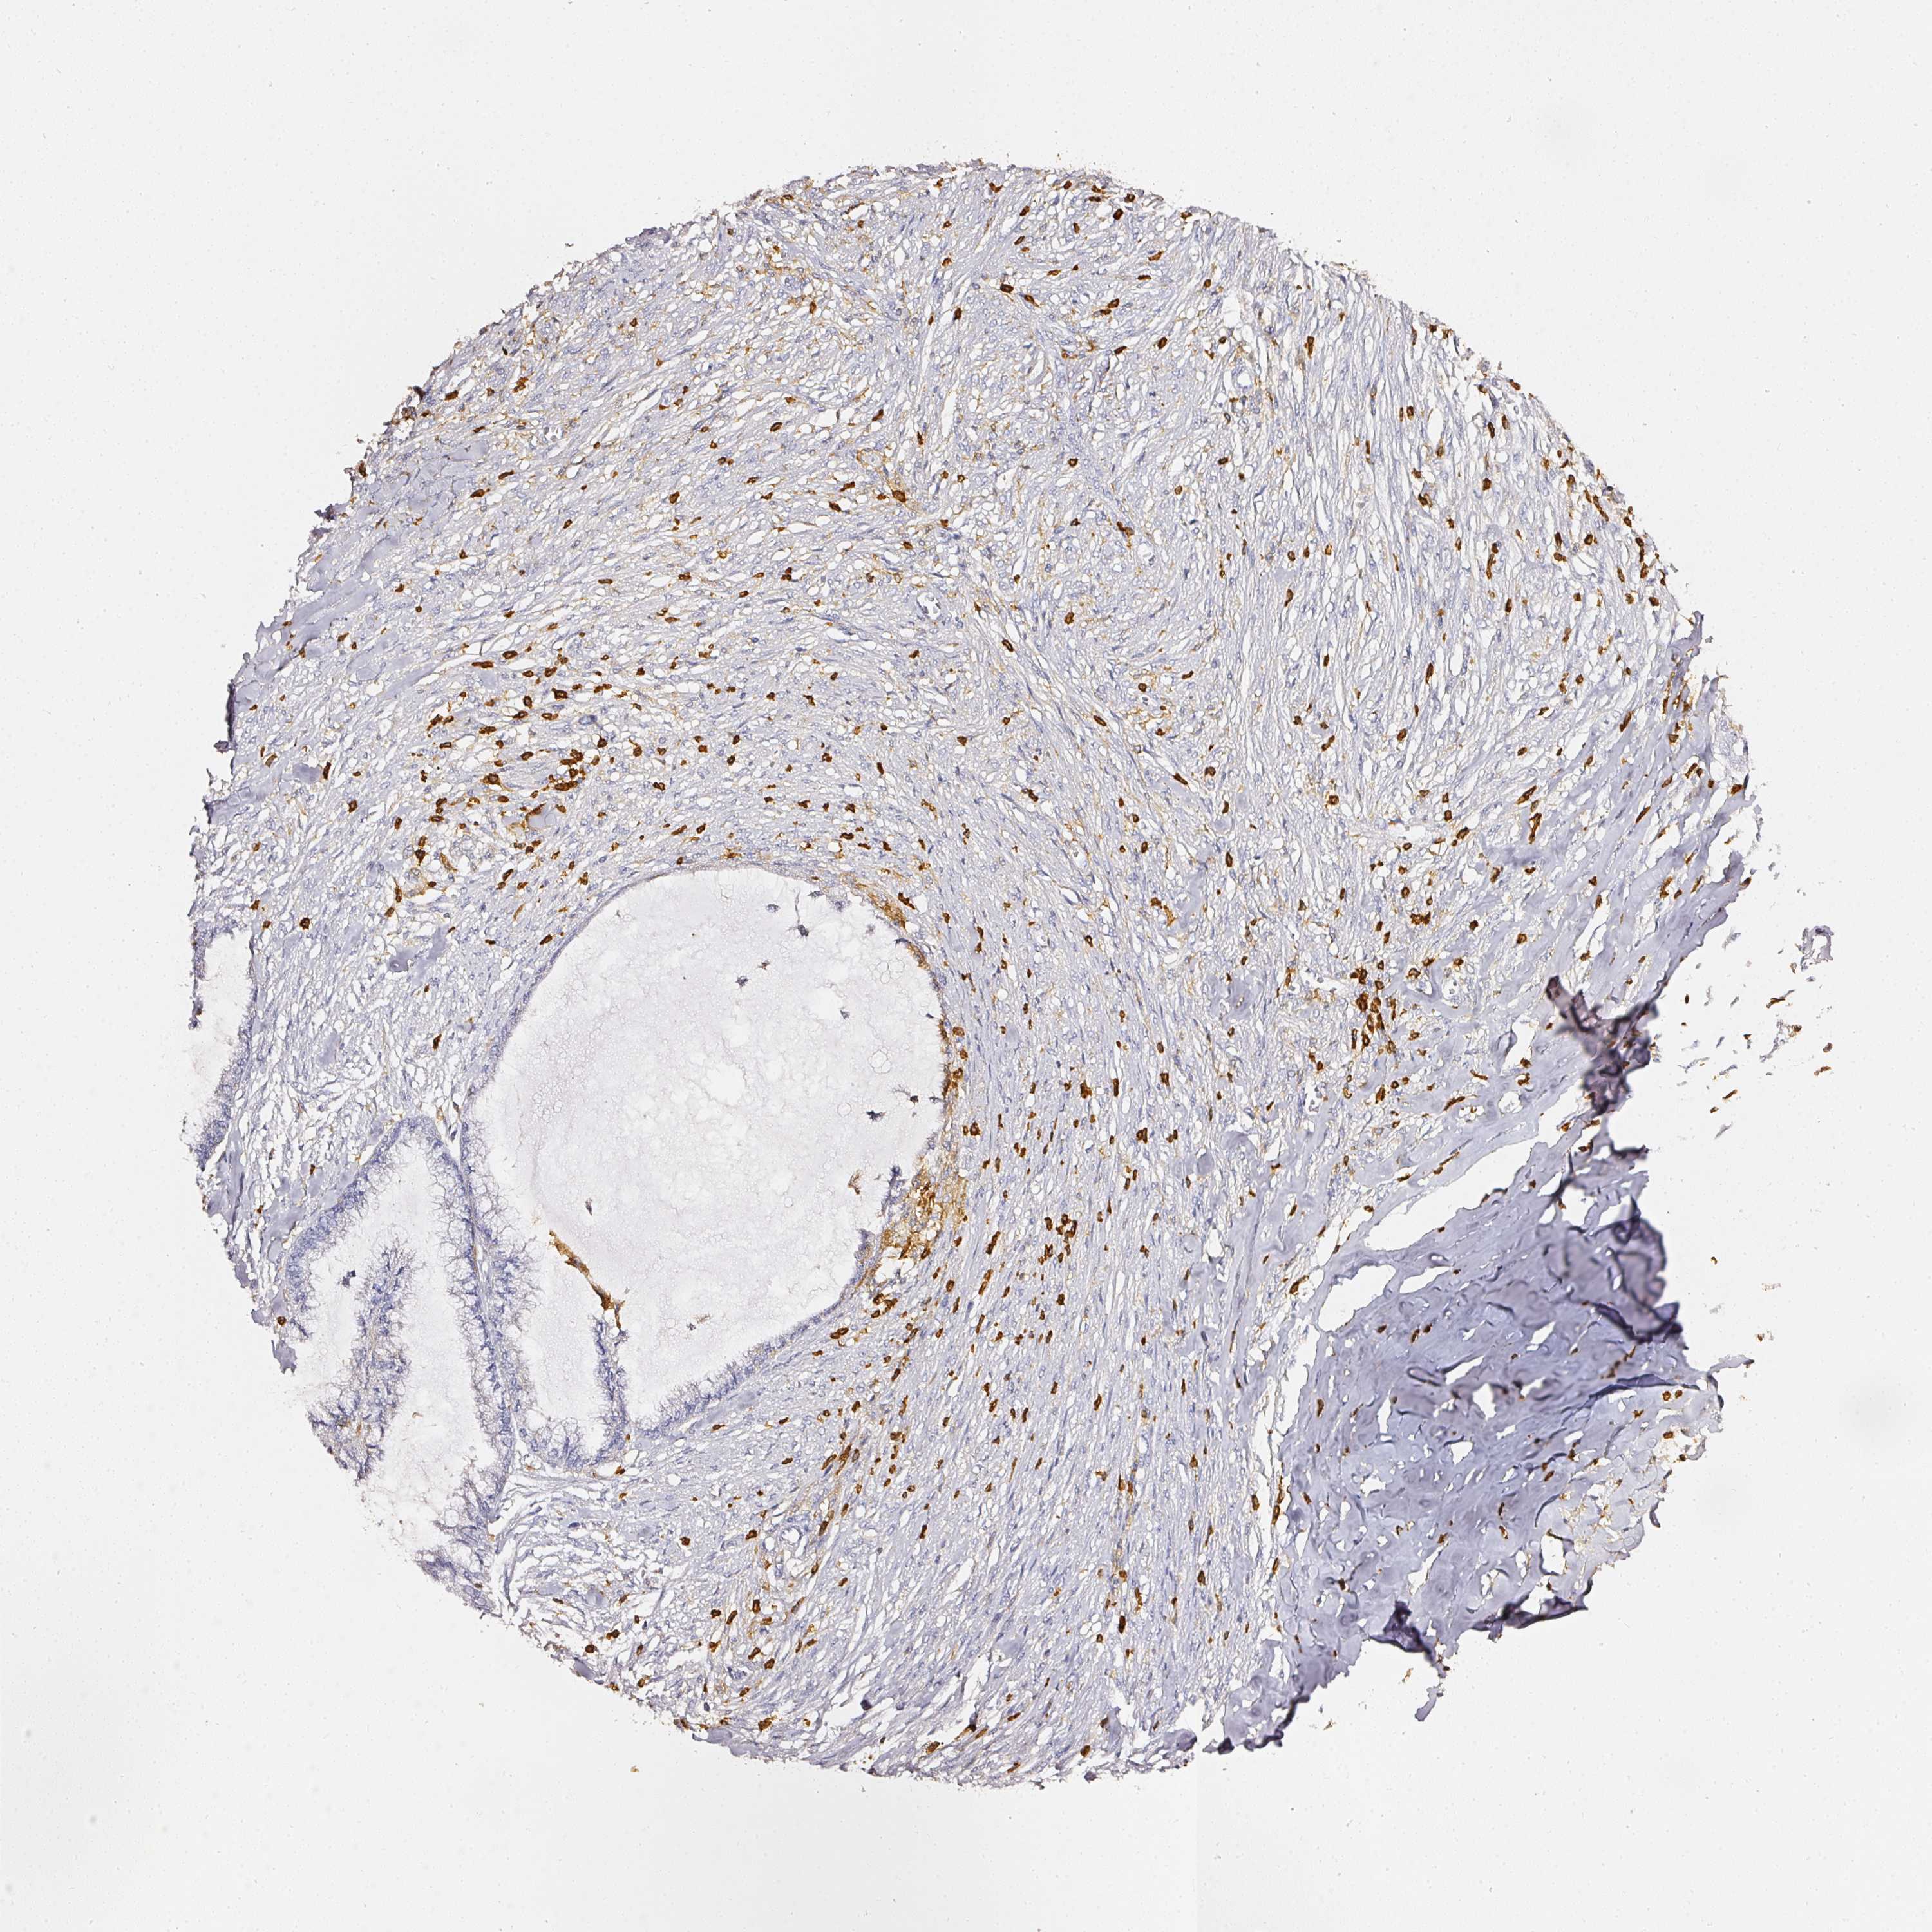

ENDOMETRIAL CANCER - Protein expressioni

A mouse-over function shows sample information and annotation data. Click on an image to view it in a full screen mode. Samples can be filtered based on level of antibody staining by selecting one or several of the following categories: high, medium, low and not detected. The assay and annotation is described here.

Note that samples used for immunohistochemistry by the Human Protein Atlas do not correspond to samples in the TCGA dataset.

Antibody stainingi

Antibody staining in the annotated cell types in the current human tissue is reported as not detected, low, medium, or high, based on conventional immunohistochemistry profiling in selected tissues. This score is based on the combination of the staining intensity and fraction of stained cells.

Each image is clickable and will lead to virtual microscopy that enables deeper exploration of all samples and also displays staining intensity scores, fraction scores and subcellular localization as well as patient and tissue information for each sample.

Antibody HPA018849

Antibody HPA019536

Antibody CAB033987

Staining

High

Medium

Low

Not detected

Intensity

Strong

Moderate

Weak

Negative

Quantity

>75%

75%-25%

<25%

None

Location

Nuclear

Cytoplasmic/membranous

Cytoplasmic/membranous,nuclear